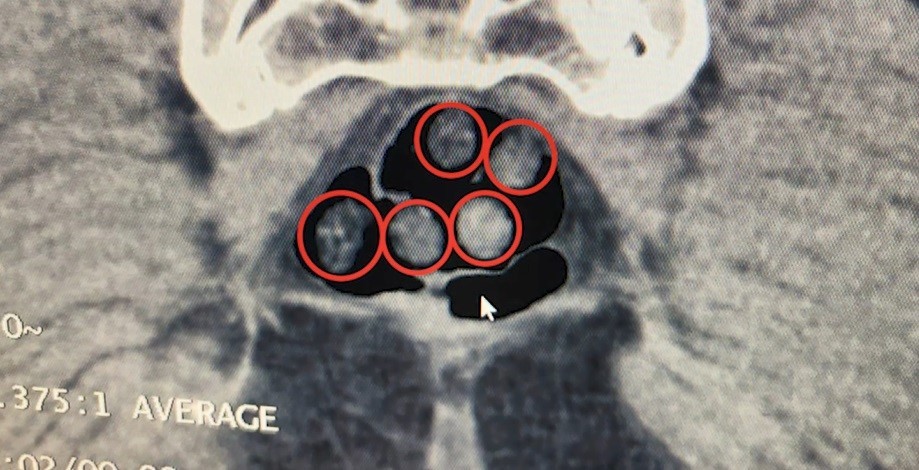

Bitlis Valiliğinden yapılan açıklamada, Bitlis Emniyet Müdürlüğü Narkotik Suçlarla Mücadele Şube Müdürlüğü ve İstihbarat Şube Müdürlüğü ekiplerinin uyuşturucu ile mücadele kapsamında yürüttüğü iki ayrı titiz çalışmanın başarıyla sonuçlandırıldığını bildirdi. Açıklamada, "Tatvan’da durdurulan çekici üzerindeki araçta yapılan aramada; 734 gram metamfetamin maddesi ele geçirildi. Olay ile ilgili 2 şahıs gözaltına alındı. Yine Tatvan’da durdurulan bir otobüste yolcu olarak seyahat eden yabancı uyruklu 2 şahıs gözaltına alındı. Tatvan Devlet Hastanesinde yapılan röntgen ve tomografi incelemelerinde, şahısların mide ile bağırsaklarında çok sayıda yabancı cisim tespit edildi. Yapılan tıbbi müdahale ile şahısların yuttuğu 14 kapsül ve üzerlerinden 36 kapsül olmak üzere toplam 50 kapsül 385 gram metamfetamin maddesi ele geçirildi. Her iki olayda da uyuşturucu madde imal ve ticareti suçundan gözaltına alınan 4 şahıstan 3’ü çıkarıldığı adli mercilerce tutuklandı. Hemşehrilerimizin huzuru ve güvenliği için uyuşturucu madde imalatı, kaçakçılığı ve kullanımına karşı yürütülen kararlı mücadelemiz devam edecektir" denildi.